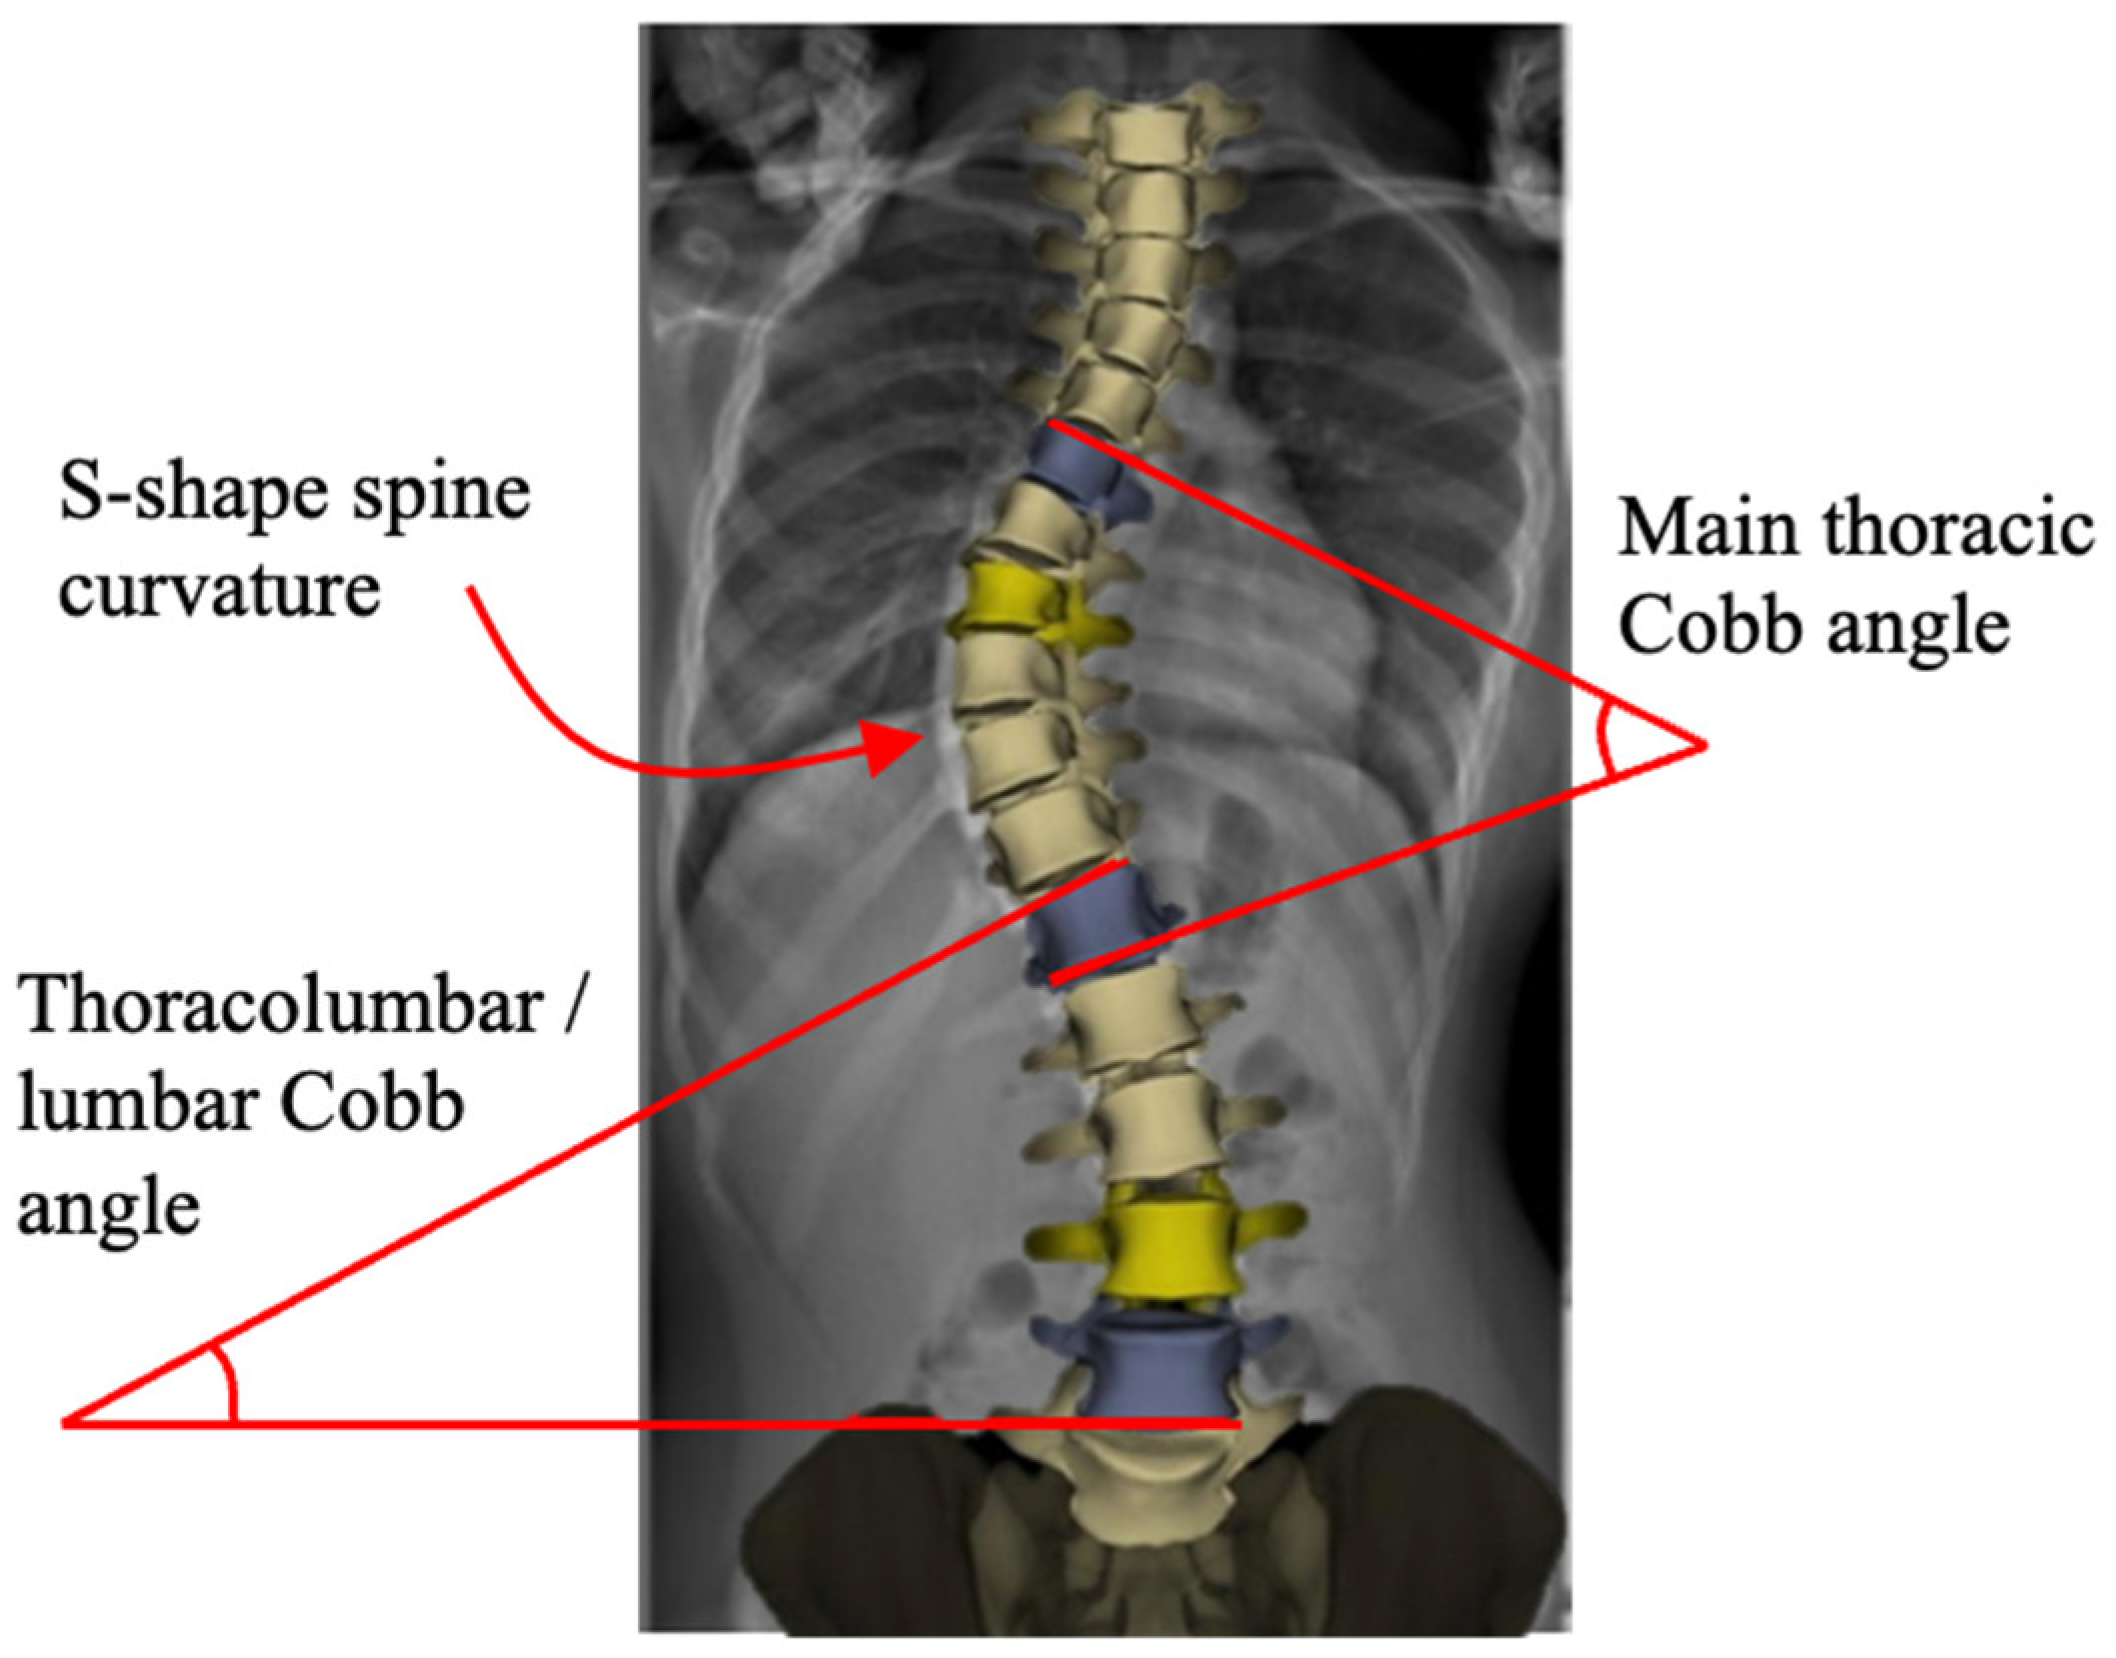

Scoliosis is a three-dimensional deformity of the spine causing S- and/or C-shape spine curvature in the coronal plane (see Figure 1) [1,2]. It is clinically characterized by the Cobb angle [3], which quantifies the level of the bending disorders of the spinal column. Scoliosis is a significant progressive musculoskeletal disorder with both physical and psychosocial implications. As scoliosis progresses, it can lead to pain, cosmetic deformity, respiratory dysfunction, and reduced quality of life. The burden of disease includes not only medical complications but also impacts on mental health, function, and long-term care [4,5]. The most common form, adolescent idiopathic scoliosis (AIS), makes up 80–85% of cases and affects between 1% and 4% of the population [6]. Management strategies vary with patient age, curve severity, and skeletal maturity [7]. Mild cases are typically managed conservatively through observation or bracing, while moderate to severe curves often require surgical correction [8]. However, the existing surgical techniques present substantial trade-offs between factors such as correction level, spinal growth, motion preservation, and stability.

Figure 1.

S-shaped scoliotic spine. Cobb angles are determined on the thoracic and lumbar spine regions. The X-rays and patients’ photos are from the patient group recruited for a project which had been approved by the domain specific review board (DSRB) and ethics committee at National University Hospital in Singapore. All patients involved in the study had been properly consulted, and their approval and informed consents were obtained.